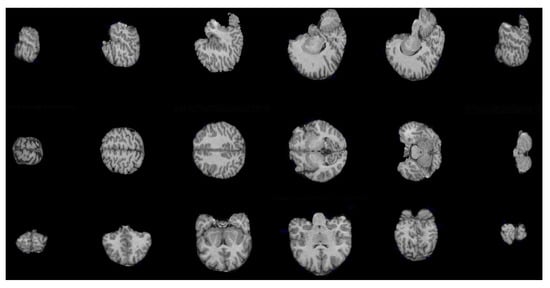

4.1. Brain Extraction Based on the Maximum Hyperconnected Function